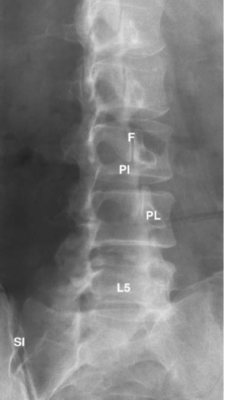

Cột sống thắt lưng

Các chữ viết tắt:

- F = Articular facet; Diện khớp nhỏ

- ID = Intervertebral disc; đĩa đệm

- L = Lamina of vertebral arch; bản cung

- L5 = L5 vertebral body; thân đốt L5

- N = Nerve root; Rễ thần kinh

- PI = Pars interarticularis; Phần liên mỏm khớp (eo)

- PL = Pedicle; cuống cung

- S = Spinal canal, cauda equina (C); ống tuỷ, đuôi ngựa

- SI = Sacroiliac joint; Khớp cùng chậu

- V =Vertebral body; Thân đốt sống